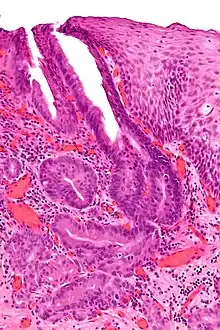

Oesophagogastric junctional adenocarcinoma (OGJ adenocarcinoma) is a cancer of the lower part of the oesophagus with a rising incidence in Western countries.[1] This disease is often linked to Barrett's oesophagus.

The diagnostic workup for OGJ adenocarcinoma usually involves performing an endoscopy with endoscopic biopsy of suspicious looking tissue. Accurate staging of tumor extent and involvement of surrounding tissue or distant metastases is critical to establishing a prognosis, and is usually guided by endoscopic ultrasound, computed tomography scans, and/or positron emission tomography scans to establish the extent of disease. Additionally, genetic analysis of the tumor may yield mutations that may be clinically significant, as described below.